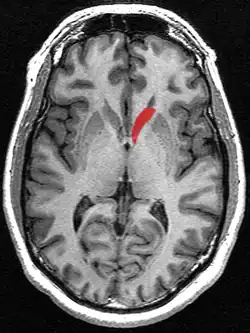

Transverse cut of brain (horizontal section), basal ganglia is blue | |

Structure

Along with the putamen, the caudate forms the dorsal striatum, which is considered a single functional structure; anatomically, it is separated by a large white-matter tract, the internal capsule, so it is sometimes also described as two structures—the medial dorsal striatum (the caudate) and the lateral dorsal striatum (the putamen). In this vein, the two are functionally distinct not because of structural differences, but merely because of the topographical distribution of function.

The caudate nuclei are near the center of the brain, sitting astride the thalamus. There is a caudate nucleus in each hemisphere of the brain. Each nucleus is C-shaped, with a wider "head" (caput in Latin) at the front, tapering to a "body" (corpus) and a "tail" (cauda). Sometimes a part of the caudate nucleus is called the "knee" (genu).[6] The caudate head receives its blood supply from the lenticulostriate artery; the tail of the caudate receives its blood supply from the anterior choroidal artery.[7]